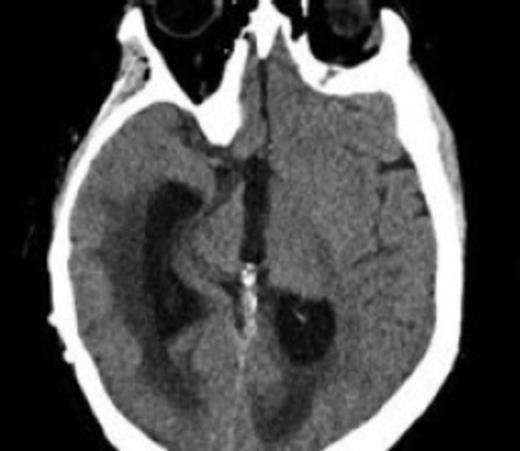

She was diagnosed with Foix-Chavany-Marie Syndrome. Scans demonstrated acute communicating hydrocephalus (Fig. 3). She was taken back to the operating room 7 days later after further workup was negative for a shunt revision to a medium pressure valve without an anti siphon device. She remained neurologically the same. Her scans showed continued ventricular enlargement and she required another trip back to the operating room for a new ventricular catheter.

CT scan showing acute enlargement of the ventricles post initial revision demonstrating shunt failure